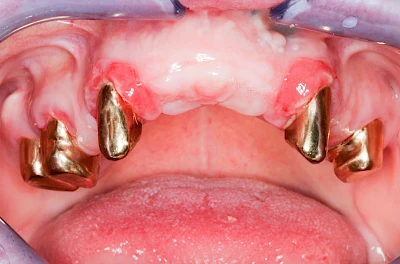

Diese Vermehrung von Bindegewebe in einem frei gewordenen Raum ist eine Sonderform der Anpassungsreaktion menschlicher Zellen und wird als Vakatwucherung bezeichnet.

Früher wurden im Unterkiefer mitunter Brücken zum Ersatz fehlender Zähne als sogenannte "Schwebebrücken" gestaltet. Die Idee dabei war, dass man die Brücke insgesamt besser reinigen kann. Allerdings war das für die Patienten mitunter irritierend für die Zunge und vor allem beim Essen gewöhnungsbedürftig. Teilweise haben sich hier reaktiv Vakatwucherungen der Kieferkammschleimhaut gebildet und den Raum unter der Brücke wieder verschlossen.